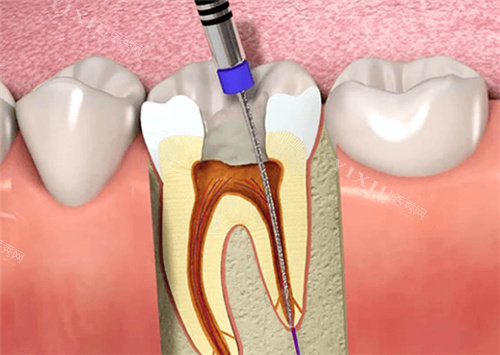

根据查询结果显示,高娅口腔确实具备合法执业资质,诊所登记类别为口腔专科门诊部,执业范围包括牙体牙髓病、牙周病、口腔修复等常规诊疗项目。

高娅医生:诊所研究人,毕业于重庆医学大学口腔医学校,从事口腔临床工作15年,擅长种植牙和美学修复。

种植牙:8000-15000元/颗